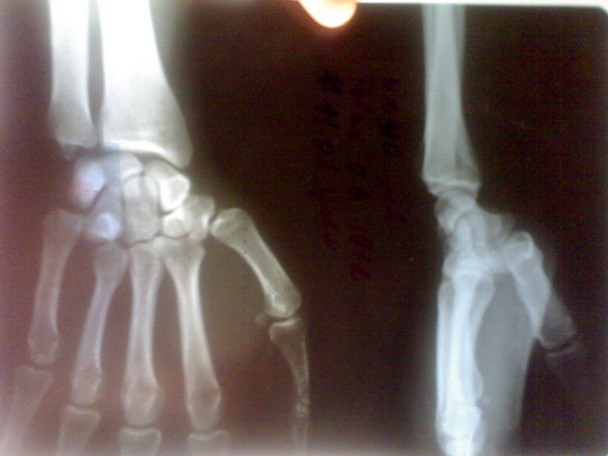

больного я направил в область. его

прооперировали. вынесены

снимки.посмотрите.

после чего некоторые говорили что это

можно было б и неоперировать

а оставить так.